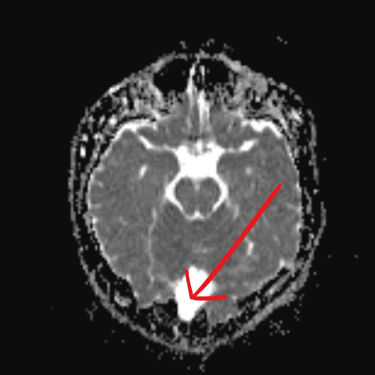

El quiste aracnoideo suboccipital es una lesión benigna de origen congénito, formada por una acumulación de líquido cefalorraquídeo entre las membranas aracnoideas. Aunque en muchos casos puede ser asintomático y detectarse de manera incidental, también puede producir cefalea, mareos, alteraciones del equilibrio o compresión del cerebelo y tronco encefálico. La resonancia magnética (RMN) es el estudio de elección, ya que permite definir la localización, tamaño y sus efectos sobre estructuras adyacentes. Este diagnóstico es clave para establecer la conducta terapéutica, que puede variar entre seguimiento clínico-radiológico o tratamiento quirúrgico en casos sintomáticos o de crecimiento progresivo.